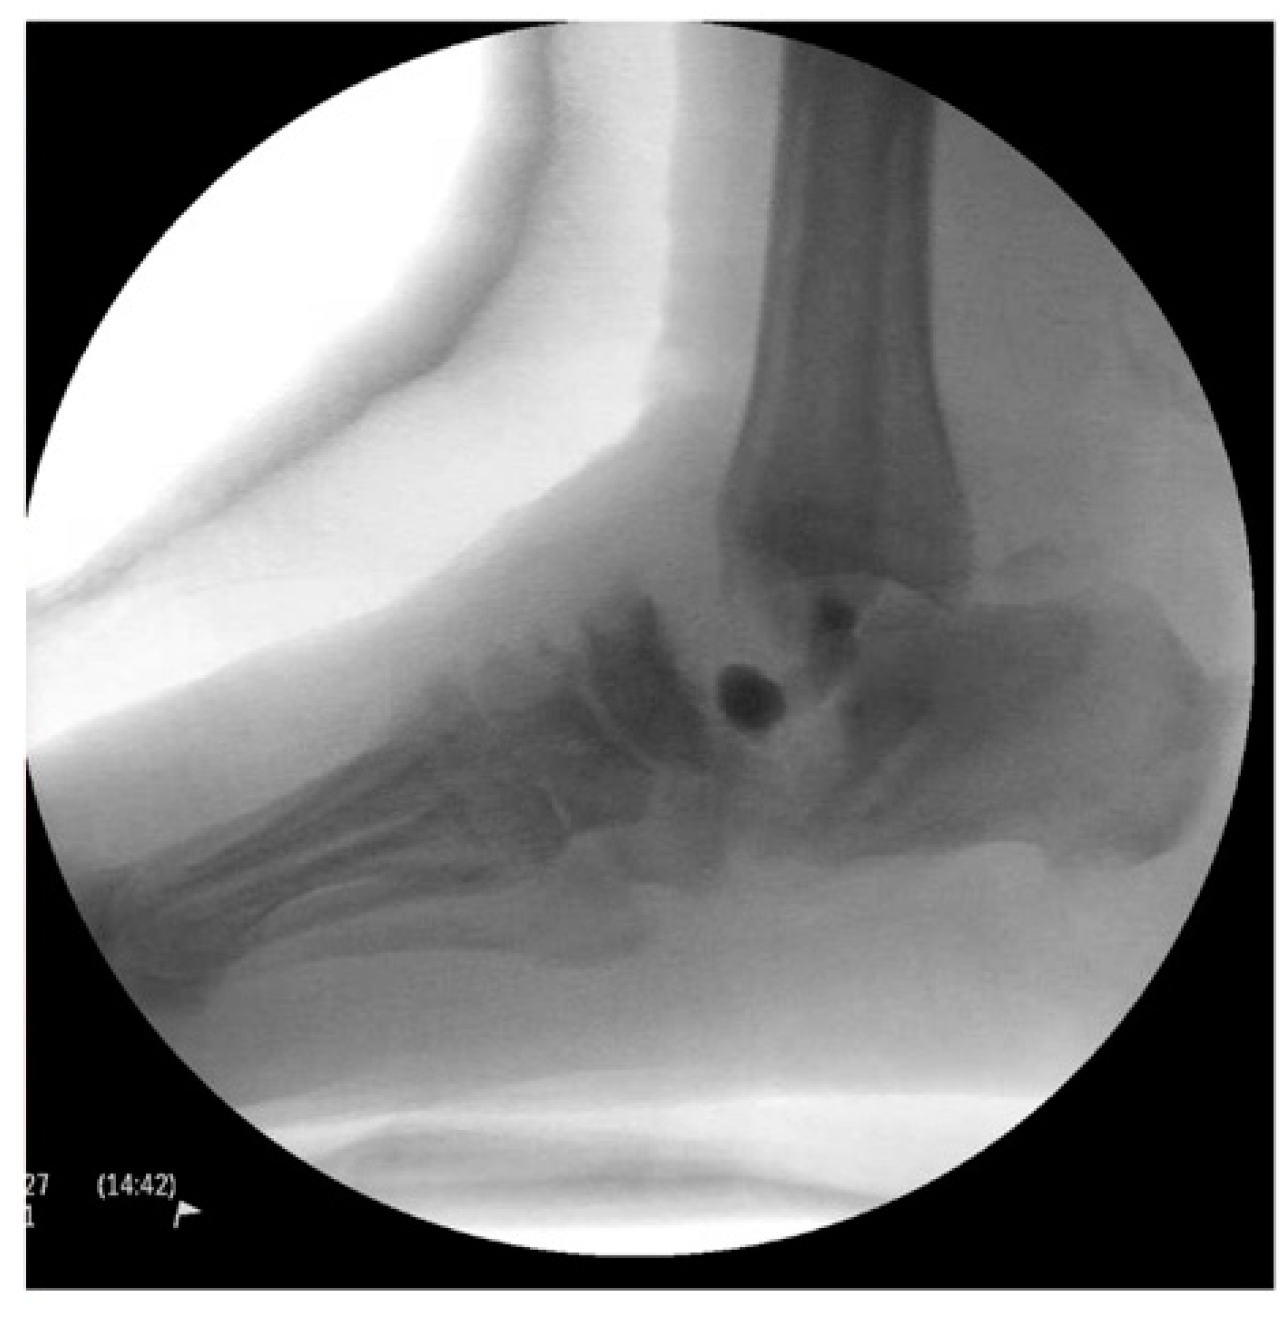

Intraoperative fluoroscopic images confirmed a complete talectomy (Figure 4). This was followed by extensive soft tissue debridement, and a thorough wound lavage. Bone and soft tissue specimens were collected for cultures. The resultant cavity was packed with antibiotic-impregnated cement beads composed of Tobramycin molded on a polydioxanone (PDS) suture. The wound was closed using a nonabsorbable monofilament suture (Figure 5). Sterile dressings were placed, followed by application of a well-padded short-leg posterior plaster splint, which was changed to a cast later (Figure 6).

Figure 4. Intraoperative radiograph.